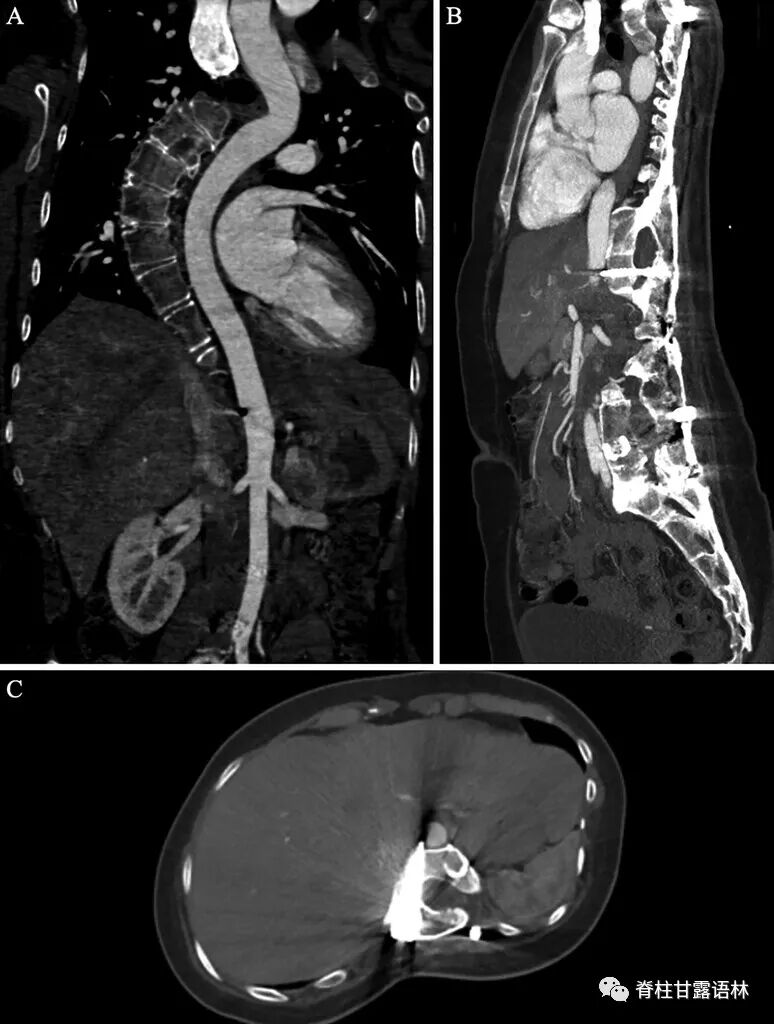

25岁时她回到诊所复查,当时她没有任何症状,否认存在背痛、腹痛、麻木、无力或步态障碍。检查时,她双侧上肢和下肢的力量和感觉完全正常。下肢血管检查显示双侧足背肌和胫后脉搏正常。站立的全脊柱X光片显示内固定无松动断裂或近端交界区后凸畸形。可观察到残余的胸腰段脊柱侧弯伴有凸起的右侧胸廓曲线和代偿性左下骨盆倾斜(图 1)。CT扫描可观察到右侧T12椎弓根螺钉尖端超出T12椎体皮质前缘5mm,进入右后外侧主动脉壁,没有血肿或假性动脉瘤的证据(图 2 )。尽管主动脉内的椎弓根螺钉尖端在临床上仍无症状,且在影像学上没有进展,但患者和她的家人选择继续进行手术干预以防止将来可能出现的并发症。

图2 通过T12椎体平面的冠状 ( A )、矢状 ( B ) 和轴向 ( C) 的CT血管造影显示右侧T12椎弓根螺钉向椎体前缘穿出。